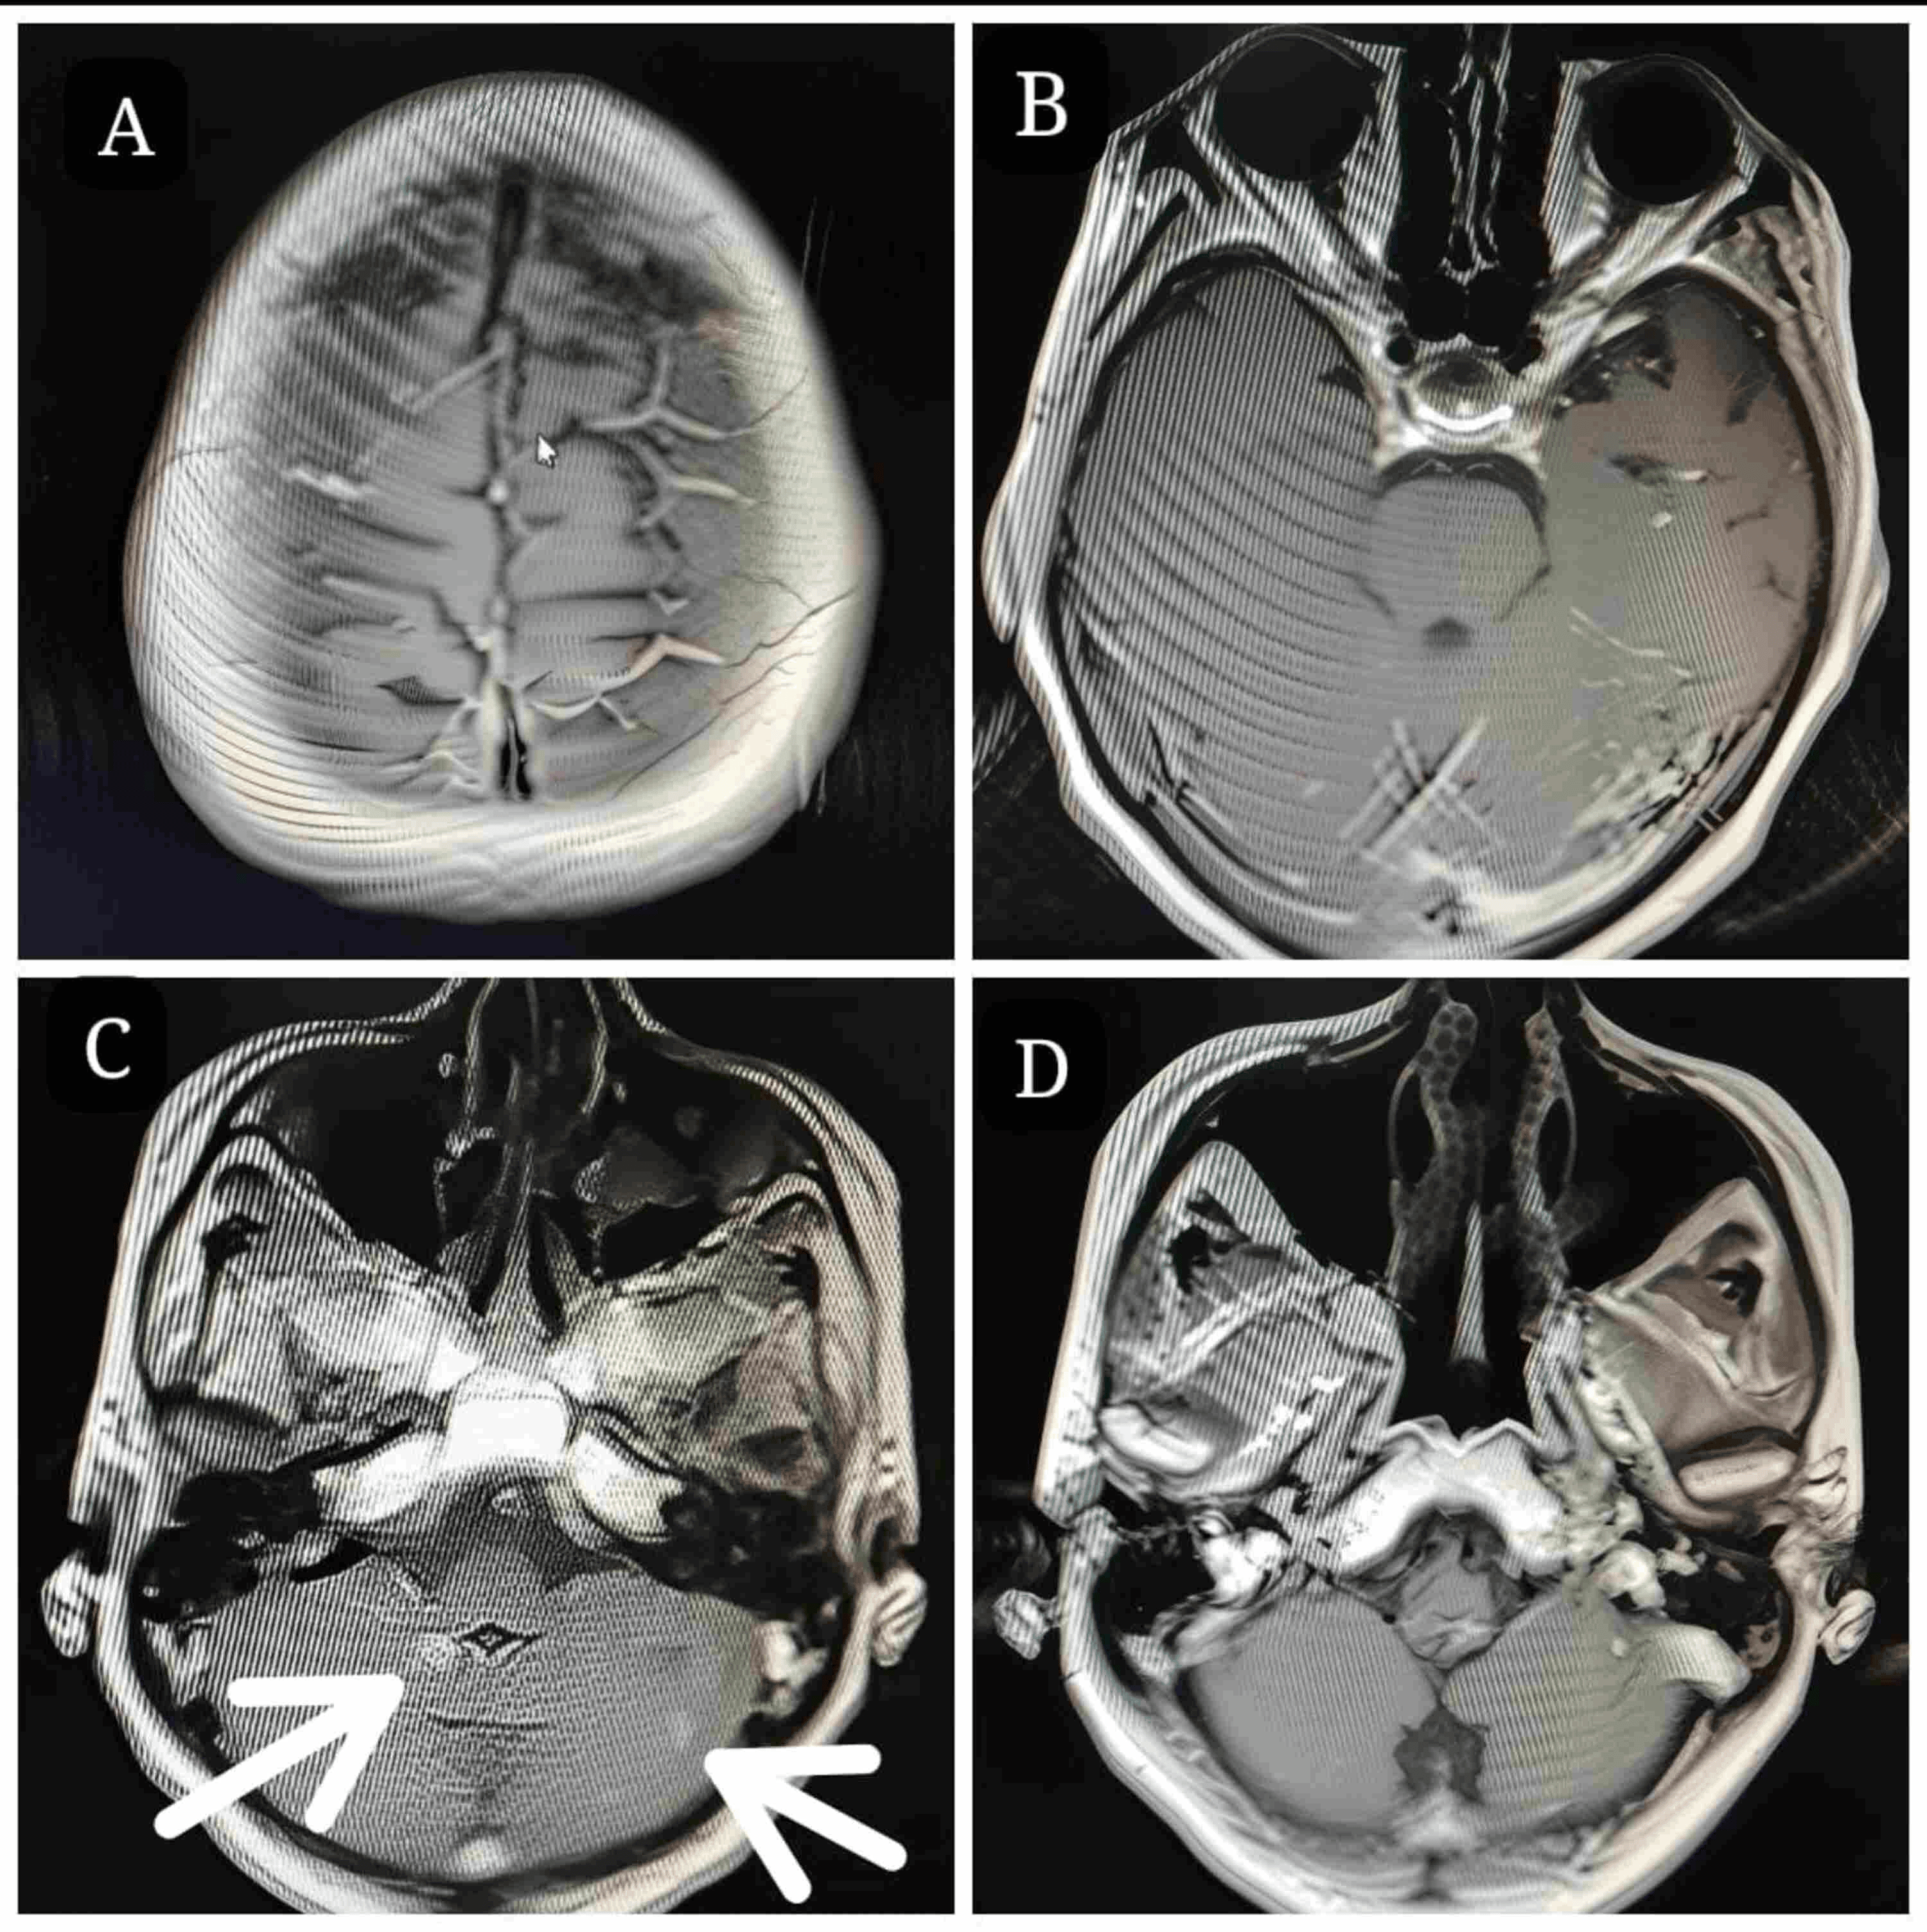

Just eight months later contrast MRI brain scans showed a remarkable overall lesion regression of 88%.

Most of the smaller intracranial lesions resolved completely, and there was a significant measurable reduction in target lesions.

A team meeting was conducted at our center with a neuroradiologist mapping 60 lesions of BMs at various locations (Video 1). The patient was classified as Eastern Cooperative Oncology Group performance status scale 0 and prepared for frameless stereotactic CyberKnife radiosurgery using Accuray Precision version 33.13(2). We chose this approach considering her comorbidities, profession, and to avoid escalating neuro-cognitive dysfunction (owing to her age and prior WBRT).